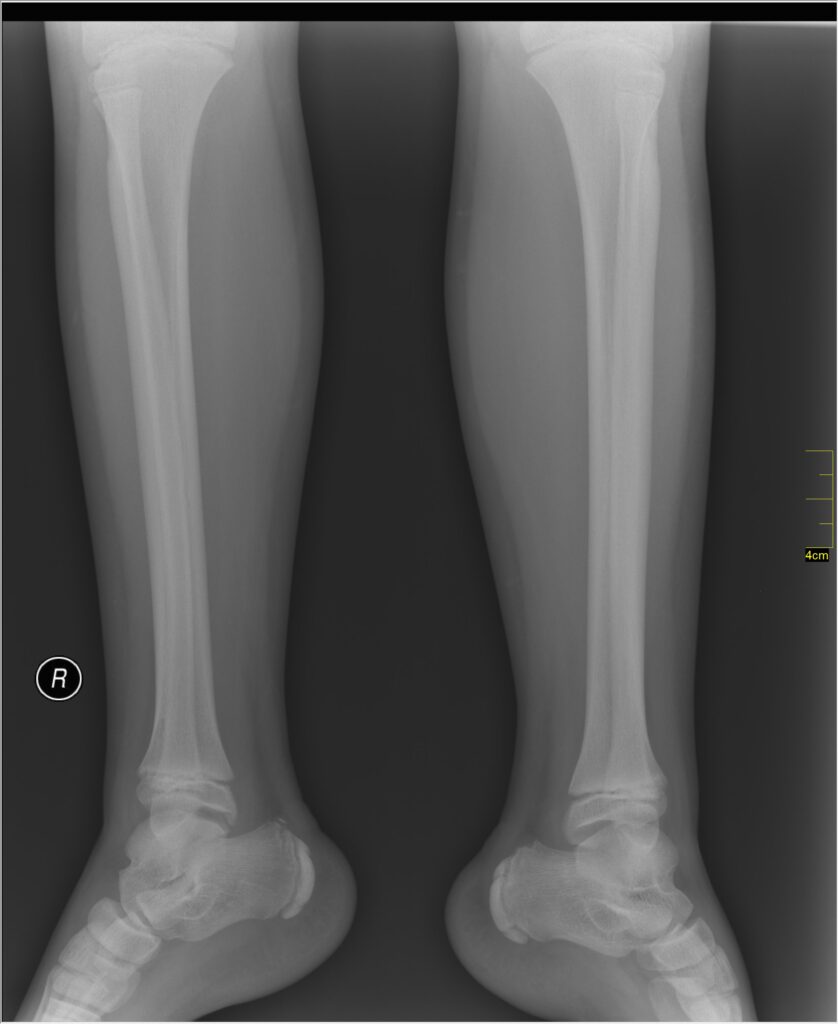

Exames de imagem mais comuns

Os principais exames que o ortopedista pode pedir são:

- Radiografia (Raio-X):

Muito usada para avaliar ossos, fraturas, desalinhamentos e deformidades. - Ultrassonografia:

Indicada principalmente para investigar problemas no quadril de bebês e crianças pequenas, como displasia ou inflamações. - Ressonância Magnética:

Ajuda a visualizar detalhes de articulações, cartilagens, músculos e tecidos moles.

Útil quando há suspeita de problemas como lesões ligamentares ou infecções ósseas.

- Tomografia Computadorizada:

Usada em casos mais complexos, como fraturas de difícil visualização.